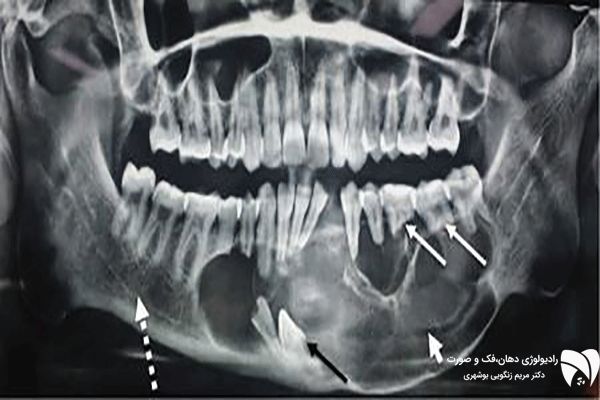

فتوگرافی ارتودنسی شامل عکس هایی از زاویه های مختلف چهره و دندانهاست که باید بسیار دقیق و با کیفیت واز زاویای استاندارد تهیه شود . فتوگرافی ارتودنسی اسکن دقیقی از وضعیت و پارامترهای چهره ، طرح لبخند و دندان های شما به دندانپزشک می دهد و به او کمک می کند تا برای شما بهترین طرح درمان متناسب با پارامترهای صورت طراحی کند و همین طور فرایند پیشرفت درمان را کنترل نماید. با توجه به اهمیت فتوگرافی دندان، بیماران باید در انتخاب بهترین رادیولوژی دهان، فک و صورت دقت بیشتری داشته باشند.

گاهی اوقات در معاینه اولیه دندانپرشک متوجه نقایص و مشکلات بیمار خود نمی شود . فتوگرافی دندان پزشکی و ارتودنسی کمک می کند تا دندانپزشک به دید کلی از وضعیت دندان های شما دست یابد و طرح درمان مناسب ارتودنسی ، ونیرکامپوزیت ، لمینت دندان یا ایمپلنت تجویز کند .عکس پزشکی باید به گونه ای استاندارد انجام شده باشد که پزشک بتواند با استناد به آن طرح درمان دقیقی را طرح ریزی کند .

یکی از مشکلاتی که اغلب دندانپزشک ها با آن دست و پنجه نرم می کنند عدم توجیه بیمار از روند فرایند درمانی خود است . با فتوگرافی می توان مشکل را حل کرد و بیمار را تا حد زیادی از کیفیت درمان خود آگاه کرد .با فتوگرافی می توان نتایج را آنالیز کرد و آن را با وضعیت فعلی بیمار مقایسه کرد تا پزشک و بیمار بتوانند به یک طرح درمان مشترک و قابل پذیرش برسند .